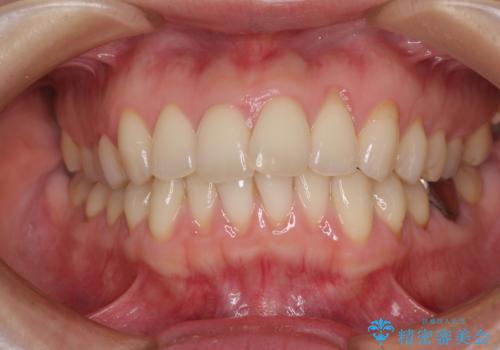

- 上下の前歯のデコボコを気にして来院された患者様です。

妊娠中であり、途中通院が難しくなる可能性があることから、インビザラインによる矯正治療を行うこととしました。

上下顎歯列全体の後方移動とIPR(歯と歯の間を削る)によってデコボコが解消するように設計しました。